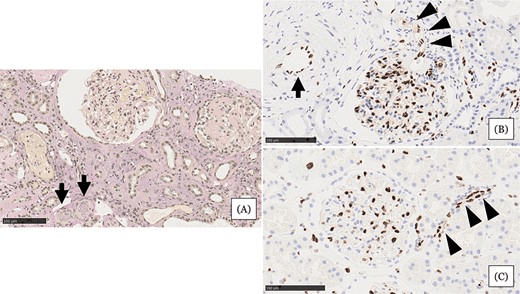

- 腎活檢示小動脈嚴重狹窄或阻塞,內皮損害嚴重,腎小球萎縮,間質細胞浸潤(圖1A)

- 與血壓正常的正常腎組織相比,血管內皮細胞(EC)細胞核等長排列整齊(圖1C)

- 患者腎組織中EC細胞核大小不一,細胞核明顯,小動脈內細胞核較少(圖1B)